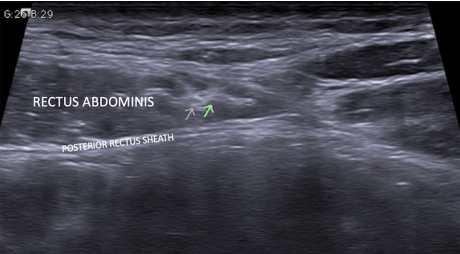

Spectrum of abdominal anterior cutaneous nerve entrapment syndrome (ACNES) with successful management: a case report

Abdominal pain is a common symptom with a spectrum of causes. Anterior cutaneous nerve entrapment syndrome (ACNES) is a commonly overlooked and underdiagnosed cause for anterior abdominal pain. Among the patients of chronic abdominal wall pain, the incidence of ACNES is 10–30% and the most common cause is nerve entrapment at the lateral border of the rectus muscle. We describe two cases covering varied location of entrapment, one at the medial border of rectus and another at lateral border explaining the need of ultrasound for successful management of both. This case report illustrates the difficulty of making this diagnosis, utility of ultrasound and a brief review of literature.